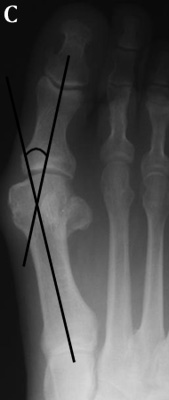

The hallux

valgus angle (HAV) or hallux abductus angle is the angle formed between the longitudinal

axis of the first proximal phalanx and the longitudinal axis of the first metatarsus.

A. In hallux varus or adductus the HAV is less then 5º. B. In normal

subjects HAV is 5º to 15º . Hallux abducto valgus is mild when HAV is 16º to